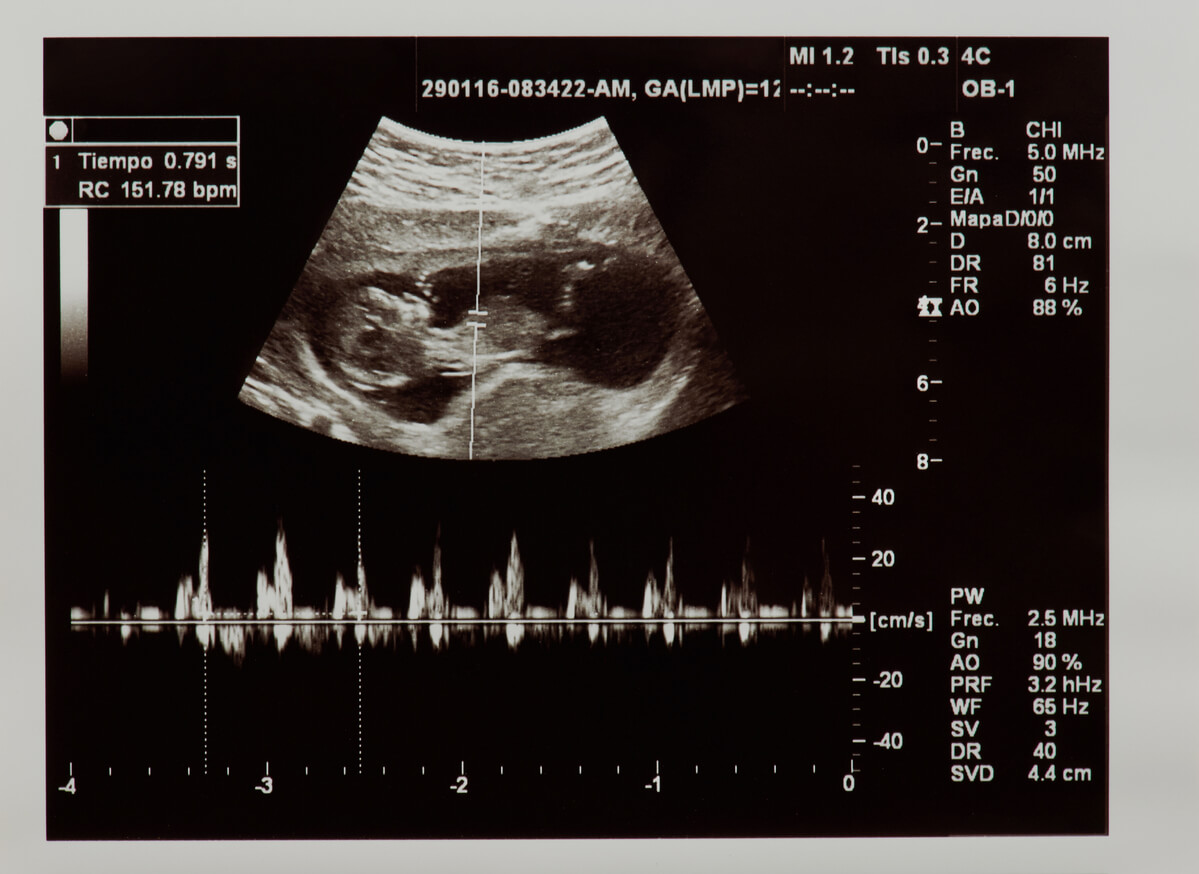

Uno de los primeros parámetros que valora el especialista al confirmar el embarazo mediante una ecografía, son los latidos del feto en el vientre de su madre. Escucharlos se convierte en uno de los momentos más emotivos, pues de esta manera se comprueba que hay un bebé formándose en su interior

Entendemos por frecuencia cardíaca el número de veces que el corazón se contrae durante un minuto. La frecuencia cardíaca fetal es identificable en las primeras semanas de gestación mediante una ecografía o un monitor conocido como Doppler fetal.

En un primer momento, se valora si efectivamente está presente el latido, con lo que se comprueba la vitalidad fetal. Además, se evalúa cuántas veces late el corazón durante un minuto. Los valores considerados normales en la etapa fetal están entre los 120 y los 160 latidos por minuto.